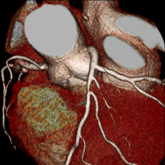

冠動脈狭窄症例